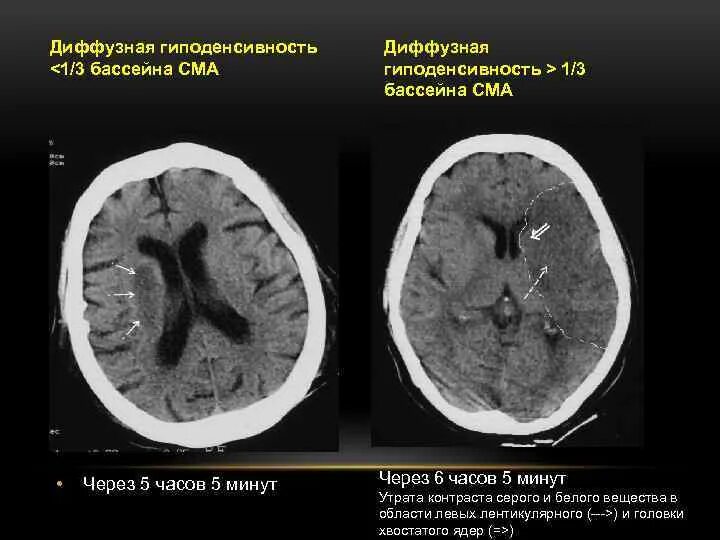

Онмк в бассейне сма